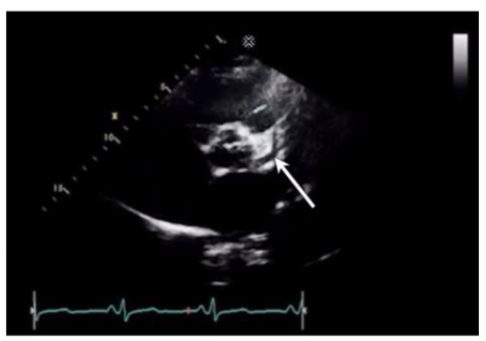

Which coronary artery is identified by the arrow on this image?

The arrow points to the left anterior descending (LAD) coronary artery, which runs in the anterior interventricular groove toward the apex of the heart. It supplies the anterior wall of the left ventricle.

The right coronary artery runs in the right atrioventricular groove. The left main coronary artery is proximal to the LAD and circumflex arteries. The circumflex artery runs in the left atrioventricular groove posteriorly.